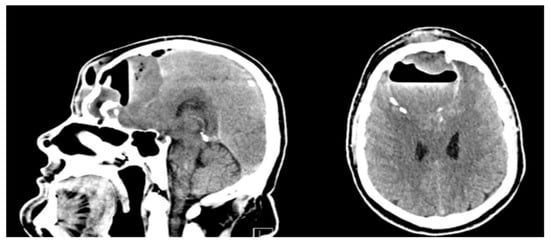

2. Case Presentation

5.5. Radiological Imaging